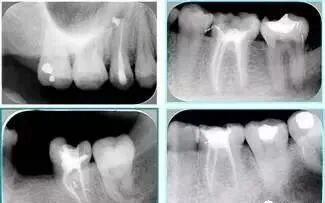

共有 4 张 X 线片,分别是术前、诊断丝 、主牙胶尖确认、术后。

( 1 )术前:术前 X 线片用来了解牙齿的大概情况。术前预期为多根牙时 X 线片应偏头拍摄。

( 2 )诊断丝:根据术前 X 线片进行开髓、根管的初步预备后,需要插入诊断丝,用来指示工作器械位置。常用 10 号或 15 号扩大器作为诊断丝插入牙髓腔。

( 3 )主牙胶尖确认:通过术前预期和诊断丝诊断,明确工作长度、牙根走向,进行根管预备。之后应进行主牙胶尖(中锉)确认,已明确根管是否适合充填。

( 4 )术后:观察治疗效果。